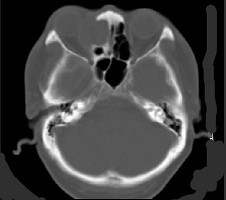

辅助检查中最有意义的发现是(如图)()